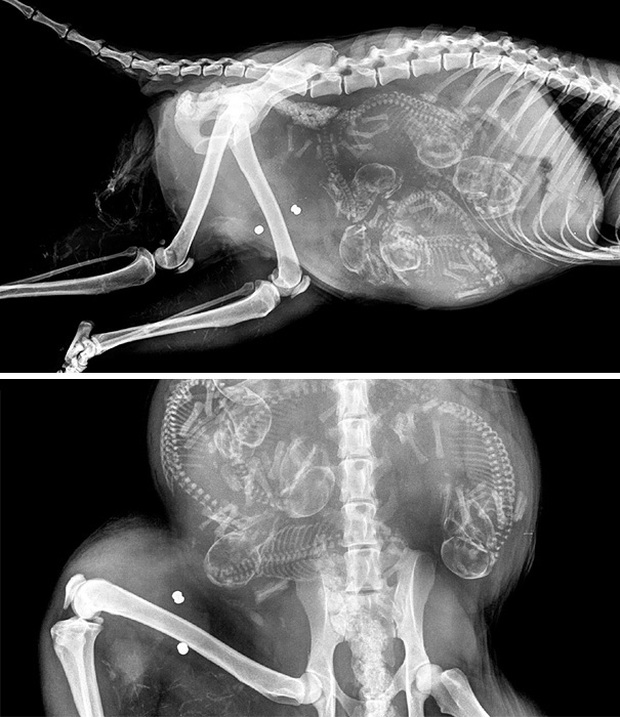

Trông có vẻ như các bé cún rất đông mà bụng chó mẹ thì lại chật hẹp. Thời gian thai của những chú cún hình thành và làm tổ ở sừng tử cung cho tới khi ra đời là khoảng 58 - 68 ngày (trung bình là 9 tuần). Những chú chó càng ít thai (dưới 4 con) thì thời gian mang thai càng dài.

Cận cảnh hình chụp X-quang một cô mèo đang mang thai và loạt ảnh động vật mang bầu khiến người xem rùng mình nhưng rồi thấy đẹp khó tả - Ảnh 3.